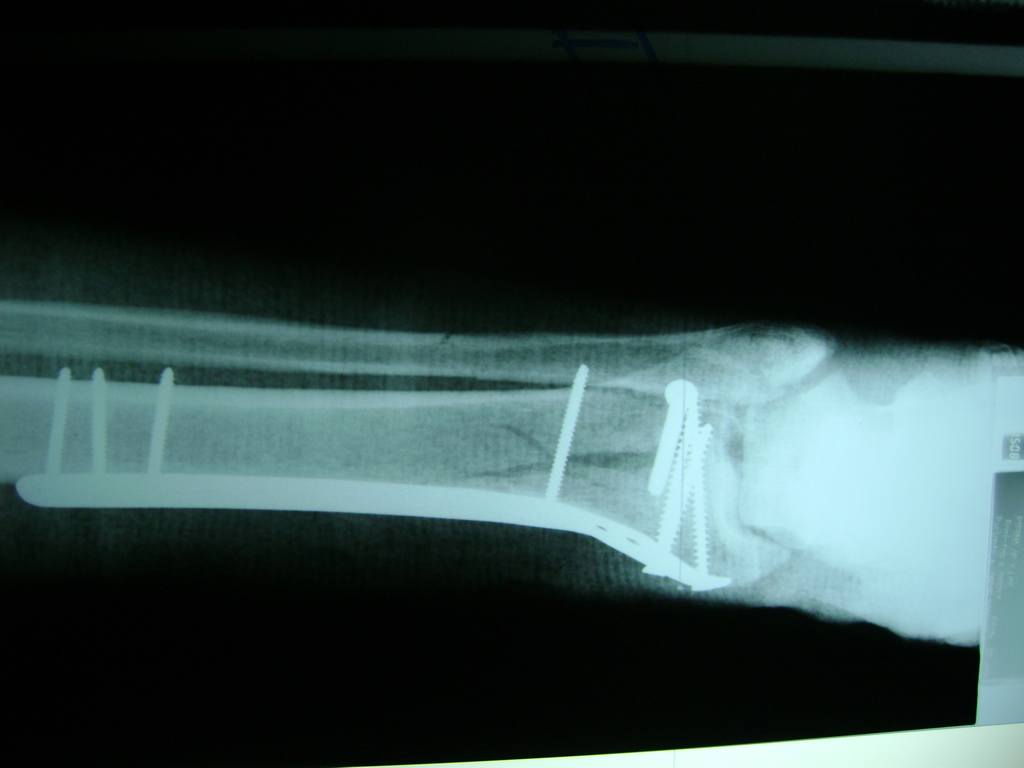

Fémur - Perone y Tibia

Aunque cada uno de estos huesos puede fracturarse por separado, normalmente la rotura es una lesión que se produce de forma conjunta

La mayor parte de las roturas implican a la parte proximal del hueso (parte del hueso próximo a la rodilla) o a la parte distal (parte del hueso cerca del tobillo).

Debido a la fina cobertura de piel que recubre la tibia y el peroné, las fracturas generalmente son abiertas, es decir, el hueso roto rasga la piel, atravesándola. Las fracturas de tibia y peroné generalmente se producen por un fuerte impacto o torsión.